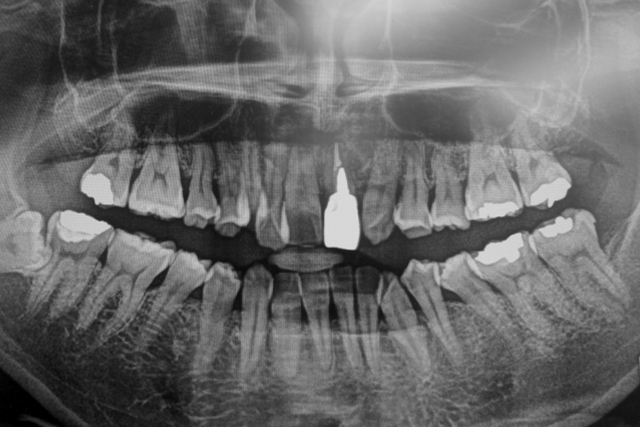

| 診療内容 | 歯科 / 小児歯科 / 口腔外科 / 矯正歯科 / 審美歯科 / ホワイトニング / 予防歯科 / インプラント / 訪問診療 |

CAD/CAMと呼ばれるコンピュータ支援設計製造ユニットを用いて製作される冠やインレー(かぶせ物、 詰め物)を用いて治療を行っています。